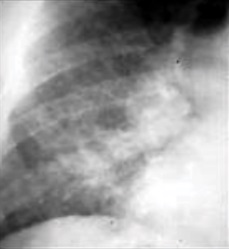

Chest x-ray of pleural thickening post-primary tuberculosis

1. Pleural thickening - Irregularity or abnormal prominence of the pleural margin, including apical capping (thickening of the pleura in the apical region). Pleural thickening can be calcified.

3. Blunting of costophrenic angle (in adults)—Loss of sharpness of one or both costophrenic angles. Blunting can be related to a small amount of fluid in the pleural space or to pleural thickening and, by itself, is a non-specific finding (except in children, when even minor blunting may suggest active TB). In contrast a large pleural effusion, or the presence of a significant amount of fluid in the pleural space, may be a sign of active TB at any age.